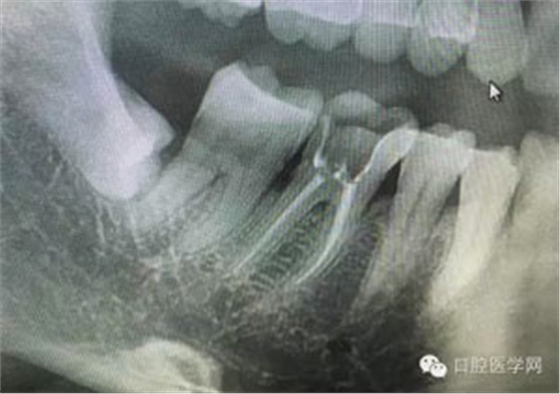

病例1:患者迫切希望保留自己的這一顆牙齒,根尖周陰影比較大,二度松動(dòng).而且旁邊有種植修復(fù)體,和患者溝通好后,治療好后觀察一個(gè)月后冠修復(fù),因?yàn)橛蟹N植的后期修復(fù),所以有了機(jī)會(huì)觀察,術(shù)后三個(gè)月和術(shù)后四個(gè)月,根尖恢復(fù)的還算不錯(cuò),希望能夠繼續(xù)觀察下去.這樣子的病例,做的時(shí)候我們一定要非常的小心,和患者要有充分的溝通以及不同科室的溝通然后決定怎么樣做比較好,假如就是出現(xiàn)了問(wèn)題,到時(shí)候我們也比較好處理些,免得我們自己到時(shí)候不好收?qǐng)觥?/span> 病例2:364647中齲的樹(shù)脂充填,現(xiàn)在樹(shù)脂的充填材料非常之多,有些時(shí)候,我們感覺(jué)有了好的材料我們就可以做出好的修復(fù),可是這是在我們有扎實(shí)的基本功的基礎(chǔ)上的,我們可以沒(méi)有那么好的樹(shù)脂,那么多的顏色選擇,修復(fù)的那么的逼真,但是我們至少要恢復(fù)患者牙齒的功能,將腐質(zhì)去除干凈,薄壁弱尖消除掉,選擇好適應(yīng)癥,給患者以盡可能好的修復(fù)。 來(lái)源于KQ88